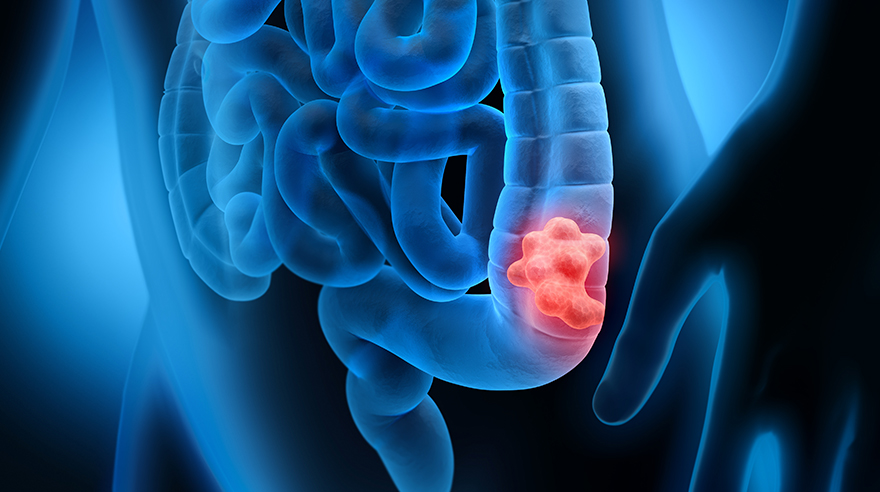

Cáncer colorrectal: La mejor prueba de detección es la que te haces tú

LEXINGTON, Ky. — El cáncer colorrectal es una de las principales causas de muertes relacionadas con el cáncer en Kentucky y, a menudo, no presenta síntomas, especialmente en sus primeras etapas. A partir de los 45 años, las pruebas de detección periódicas son la clave para prevenir esta enfermedad y detectarla a tiempo.

Hay dos tipos principales de pruebas de detección: exámenes visuales, que incluyen colonoscopias y pruebas basadas en heces. Si bien la colonoscopia es el estándar de oro para la detección, es un procedimiento invasivo que debe realizarse en una clínica u hospital bajo sedación. Las pruebas basadas en heces ofrecen una alternativa que es menos invasiva y puede ser más accesible.

Las pruebas basadas en heces buscan sangre y ADN anormal en las heces y se pueden realizar en la privacidad de su hogar. Los pacientes recolectan sus muestras utilizando un kit que devuelven a su médico o envían por correo a un laboratorio para su análisis. Estas pruebas incluyen pruebas de sangre oculta en heces (gFOBT o FIT) y pruebas de ADN en heces (Cologuard). Dependiendo del tipo de prueba que le hagan, puede haber restricciones dietéticas antes de la prueba. Todas las pruebas en el hogar deben repetirse anualmente; cualquier hallazgo positivo requiere una colonoscopia de seguimiento.